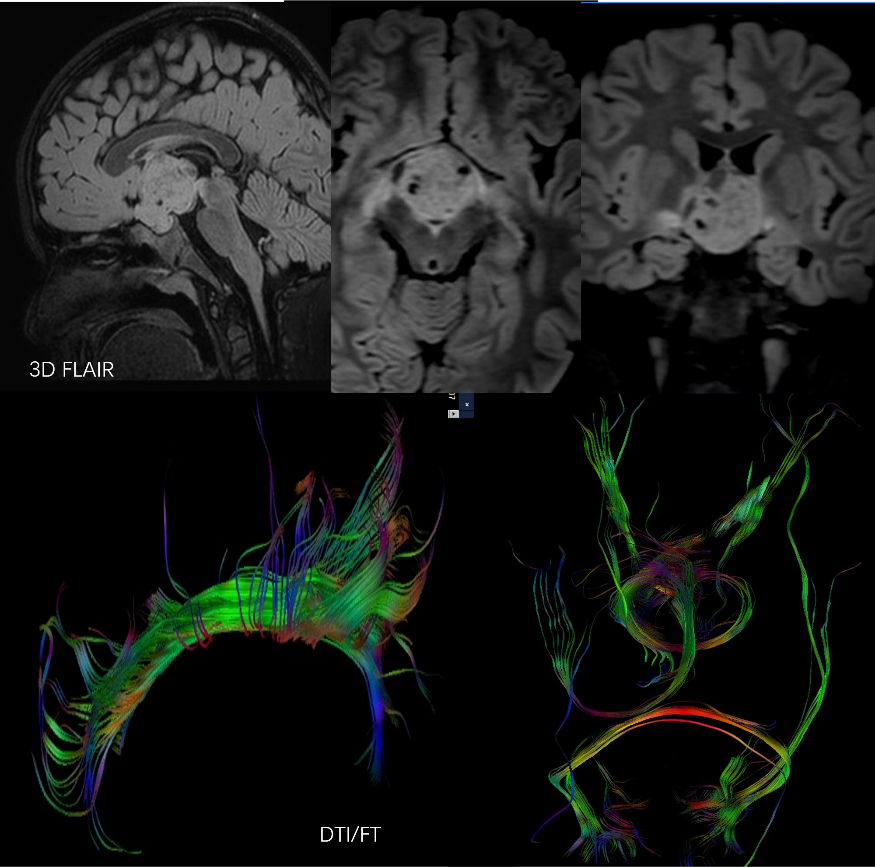

大脑结构 大脑血管及神经纤维束

脑膜瘤患者,手术前计划,通过高分辨脑表面血管与瘤体病变,脑整体结构融合,获得明确定位表征信息。 脑中线视神经乳头胶质瘤,高分辨脑神经系统3D FLAIR成像技术显示视神经乳头胶质瘤的空间三维特征,DTI及纤维示踪后处理技术显示与手术入路相关穹隆及视路神经纤维束走行及特征。